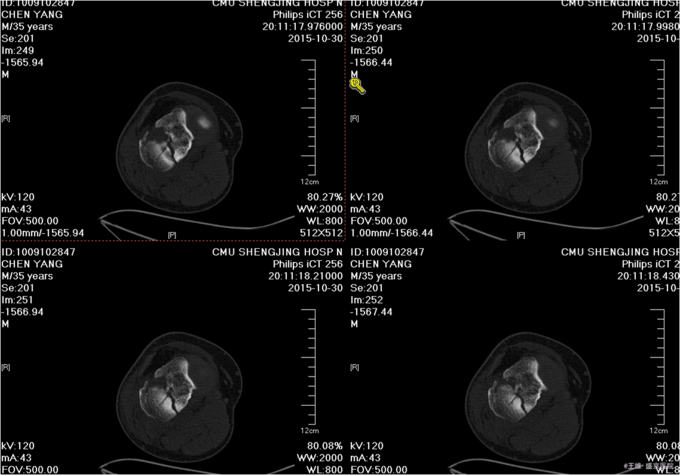

主诉:车祸致右膝部疼痛肿胀活动障碍5小时 现病史:患者及家属代述患者于2015年10月30日下午5点时在走路时被汽车撞伤发生车祸,导致右膝部疼痛肿胀活动障碍,当时无昏迷,送至沈阳中医4院,行DR及影像学检查示:右胫骨平台骨折,右12肋骨骨折。家属为行进一步治疗来我院就诊。经门诊检查后收入我科。患者病来,意识清醒,无头痛头晕,无咳嗽咳痰,无心慌气短,饮食正常,小便正常,大便未排,体重无变化。

专科查体:右小腿近端肿胀明显,无明显开放性创口,痛阳性,叩击痛阳性,可触及骨擦音骨擦感,压痛阳性,,右下肢感觉未见明显异常,右足趾感觉运动未见明显异常,双侧足背动脉搏动良好,末梢血运良好